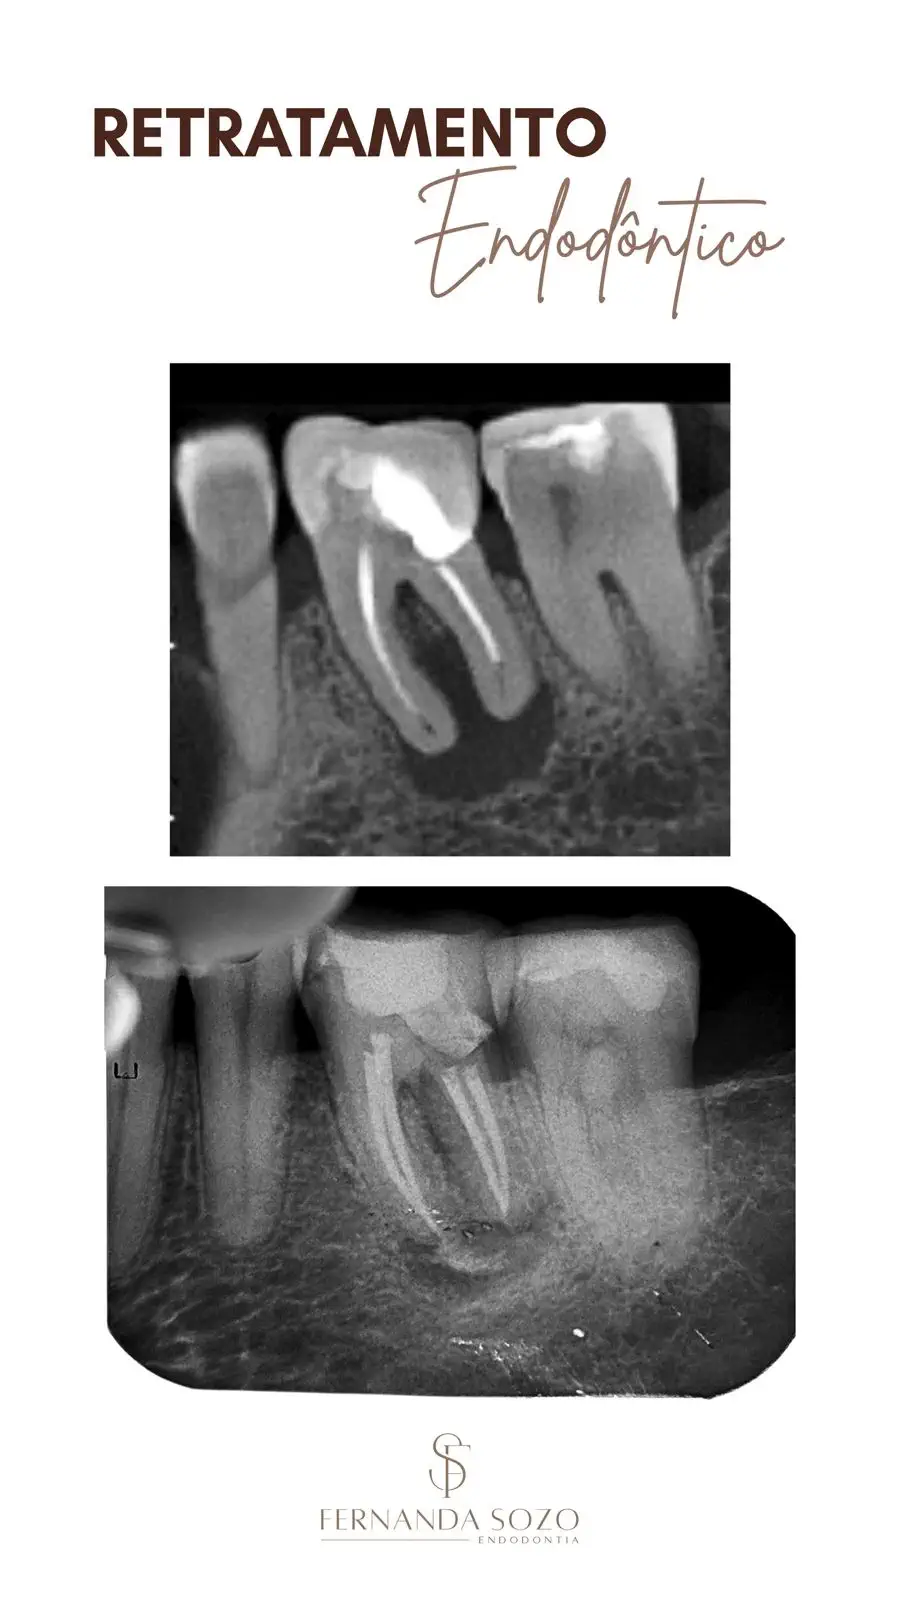

Portfólio

Casos Clínicos

Resultados que demonstram precisão técnica e excelência.